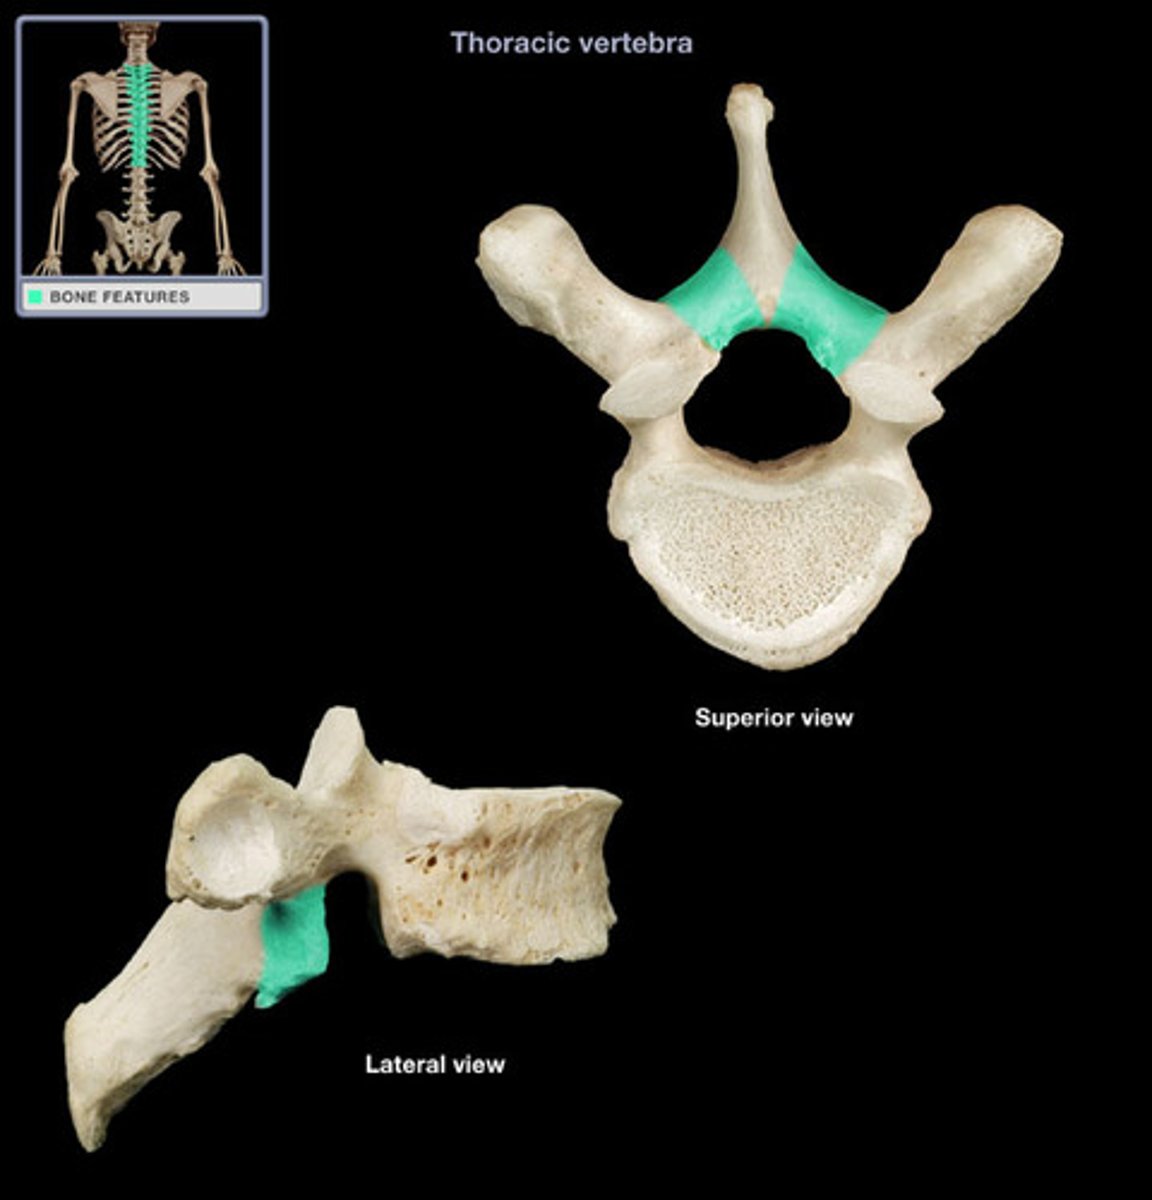

transverse costal facet

rib articulation (attachment) ONLY FOUND IN T1-T12

what is the purpose of the transverse costal facets

12 (T1-T12)

how many transverse costal facets for rib articulation (attachment) are there

transverse costal facets (articulations) where ribs attach to

what differenciates the T spine vertebra